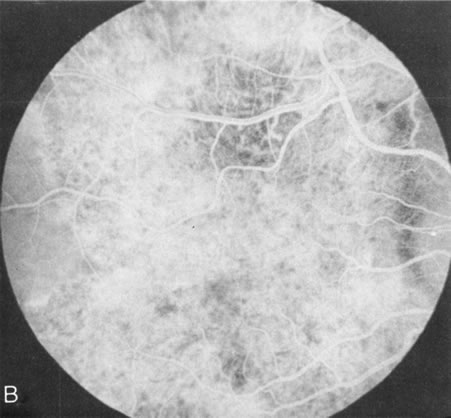

In retinitis pigmentosa (RP), the pigment abnormalities of atrophy, migration, and clumping are made apparent by transmitted hyperfluorescence and blocked hypofluorescence (Fig. 1A). Patients who have very minimal pigmentary alterations (pauci pigmentary RP) or no pigment abnormalities (RP sine pigmento) may show the abnormalities on fluorescien angiography (FA). It is uncommon to see choriocapillaris atrophy except in the late stages. This finding corresponds to the histopathology, which shows that the earliest abnormalities are in the photoreceptors and that the choroid is normal.1

Fig. 1. Retinitis pigmentosa. A. A typical area of bone spicule pigmentation. B. Diffuse dye leakage is apparent throughout the posterior pole. C. The early angiogram shows dilated and irregular retinal radial peripapillary capillaries and perifoveal retinal capillaries. D. Leakage from these vessels are evident in the late angiogram.

Dye leakage in RP may occur from the retinal vessels or at the level of the retinal pigment epithelium (Fig. 1B).2–4 The leakage may be seen in the macula and posterior pole, along the vascular arcades in the distribution of the radial peripapillary capillaries, and in the periphery (where an exudative vasculopathy resembling Coats' disease is suggested).

Of more clinical importance is the role of FA in the diagnosis and treatment of cystoid macular edema (CME) (Fig. 1C and D). Stereoscopic FA indicates that the leakage, which may be diffuse or have the typical petaloid stellate appearance of CME, can come from the perifoveal retinal capillaries, from the choroid through the RPE, or from a combination of both sources.4 With the recent suggestion that CME in RP may be successfully treated with acetazolamide,5, 6 FA is thus important to document the diagnosis of CME, establish the origin(s) of leakage, and follow patients during and after therapy.